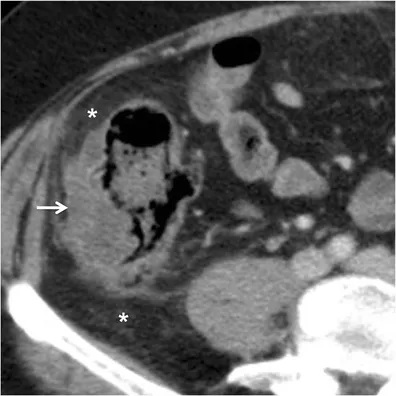

- Abdominal/Pelvic CT scan with IV contrast is the preferred imaging test.

- Key CT findings: Focal bowel wall thickening (>4 mm), pericolic fat stranding, abscess, or free air (perforation).

- Abscess: Most common complication; suspect with persistent fever despite antibiotics.